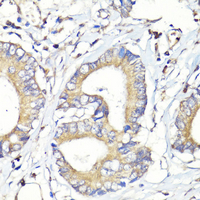

Immunohistochemical analysis of HBEGF staining in human colon cancer formalin fixed paraffin embedded tissue section. The section was pre-treated using heat mediated antigen retrieval with sodium citrate buffer (pH 6.0). The section was then incubated with the antibody at room temperature and detected using an HRP conjugated compact polymer system. DAB was used as the chromogen. The section was then counterstained with haematoxylin and mounted with DPX. Immunohistochemical analysis of HBEGF staining in human colon cancer formalin fixed paraffin embedded tissue section. The section was pre-treated using heat mediated antigen retrieval with sodium citrate buffer (pH 6.0). The section was then incubated with the antibody at room temperature and detected using an HRP conjugated compact polymer system. DAB was used as the chromogen. The section was then counterstained with haematoxylin and mounted with DPX.